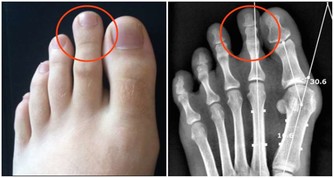

泡腳是通過水溫讓腳迅速的暖和起來,但是千萬水溫不能太高,因為太高的水溫會燙傷腳部的皮膚,輕者會發紅,重者會起水泡,我們經常會看到因為水溫過熱,皮膚被燙傷的情況。如果是糖尿病的患者更要注意水的溫度,因為他們對溫度的感應不敏感,更容易被燙傷。